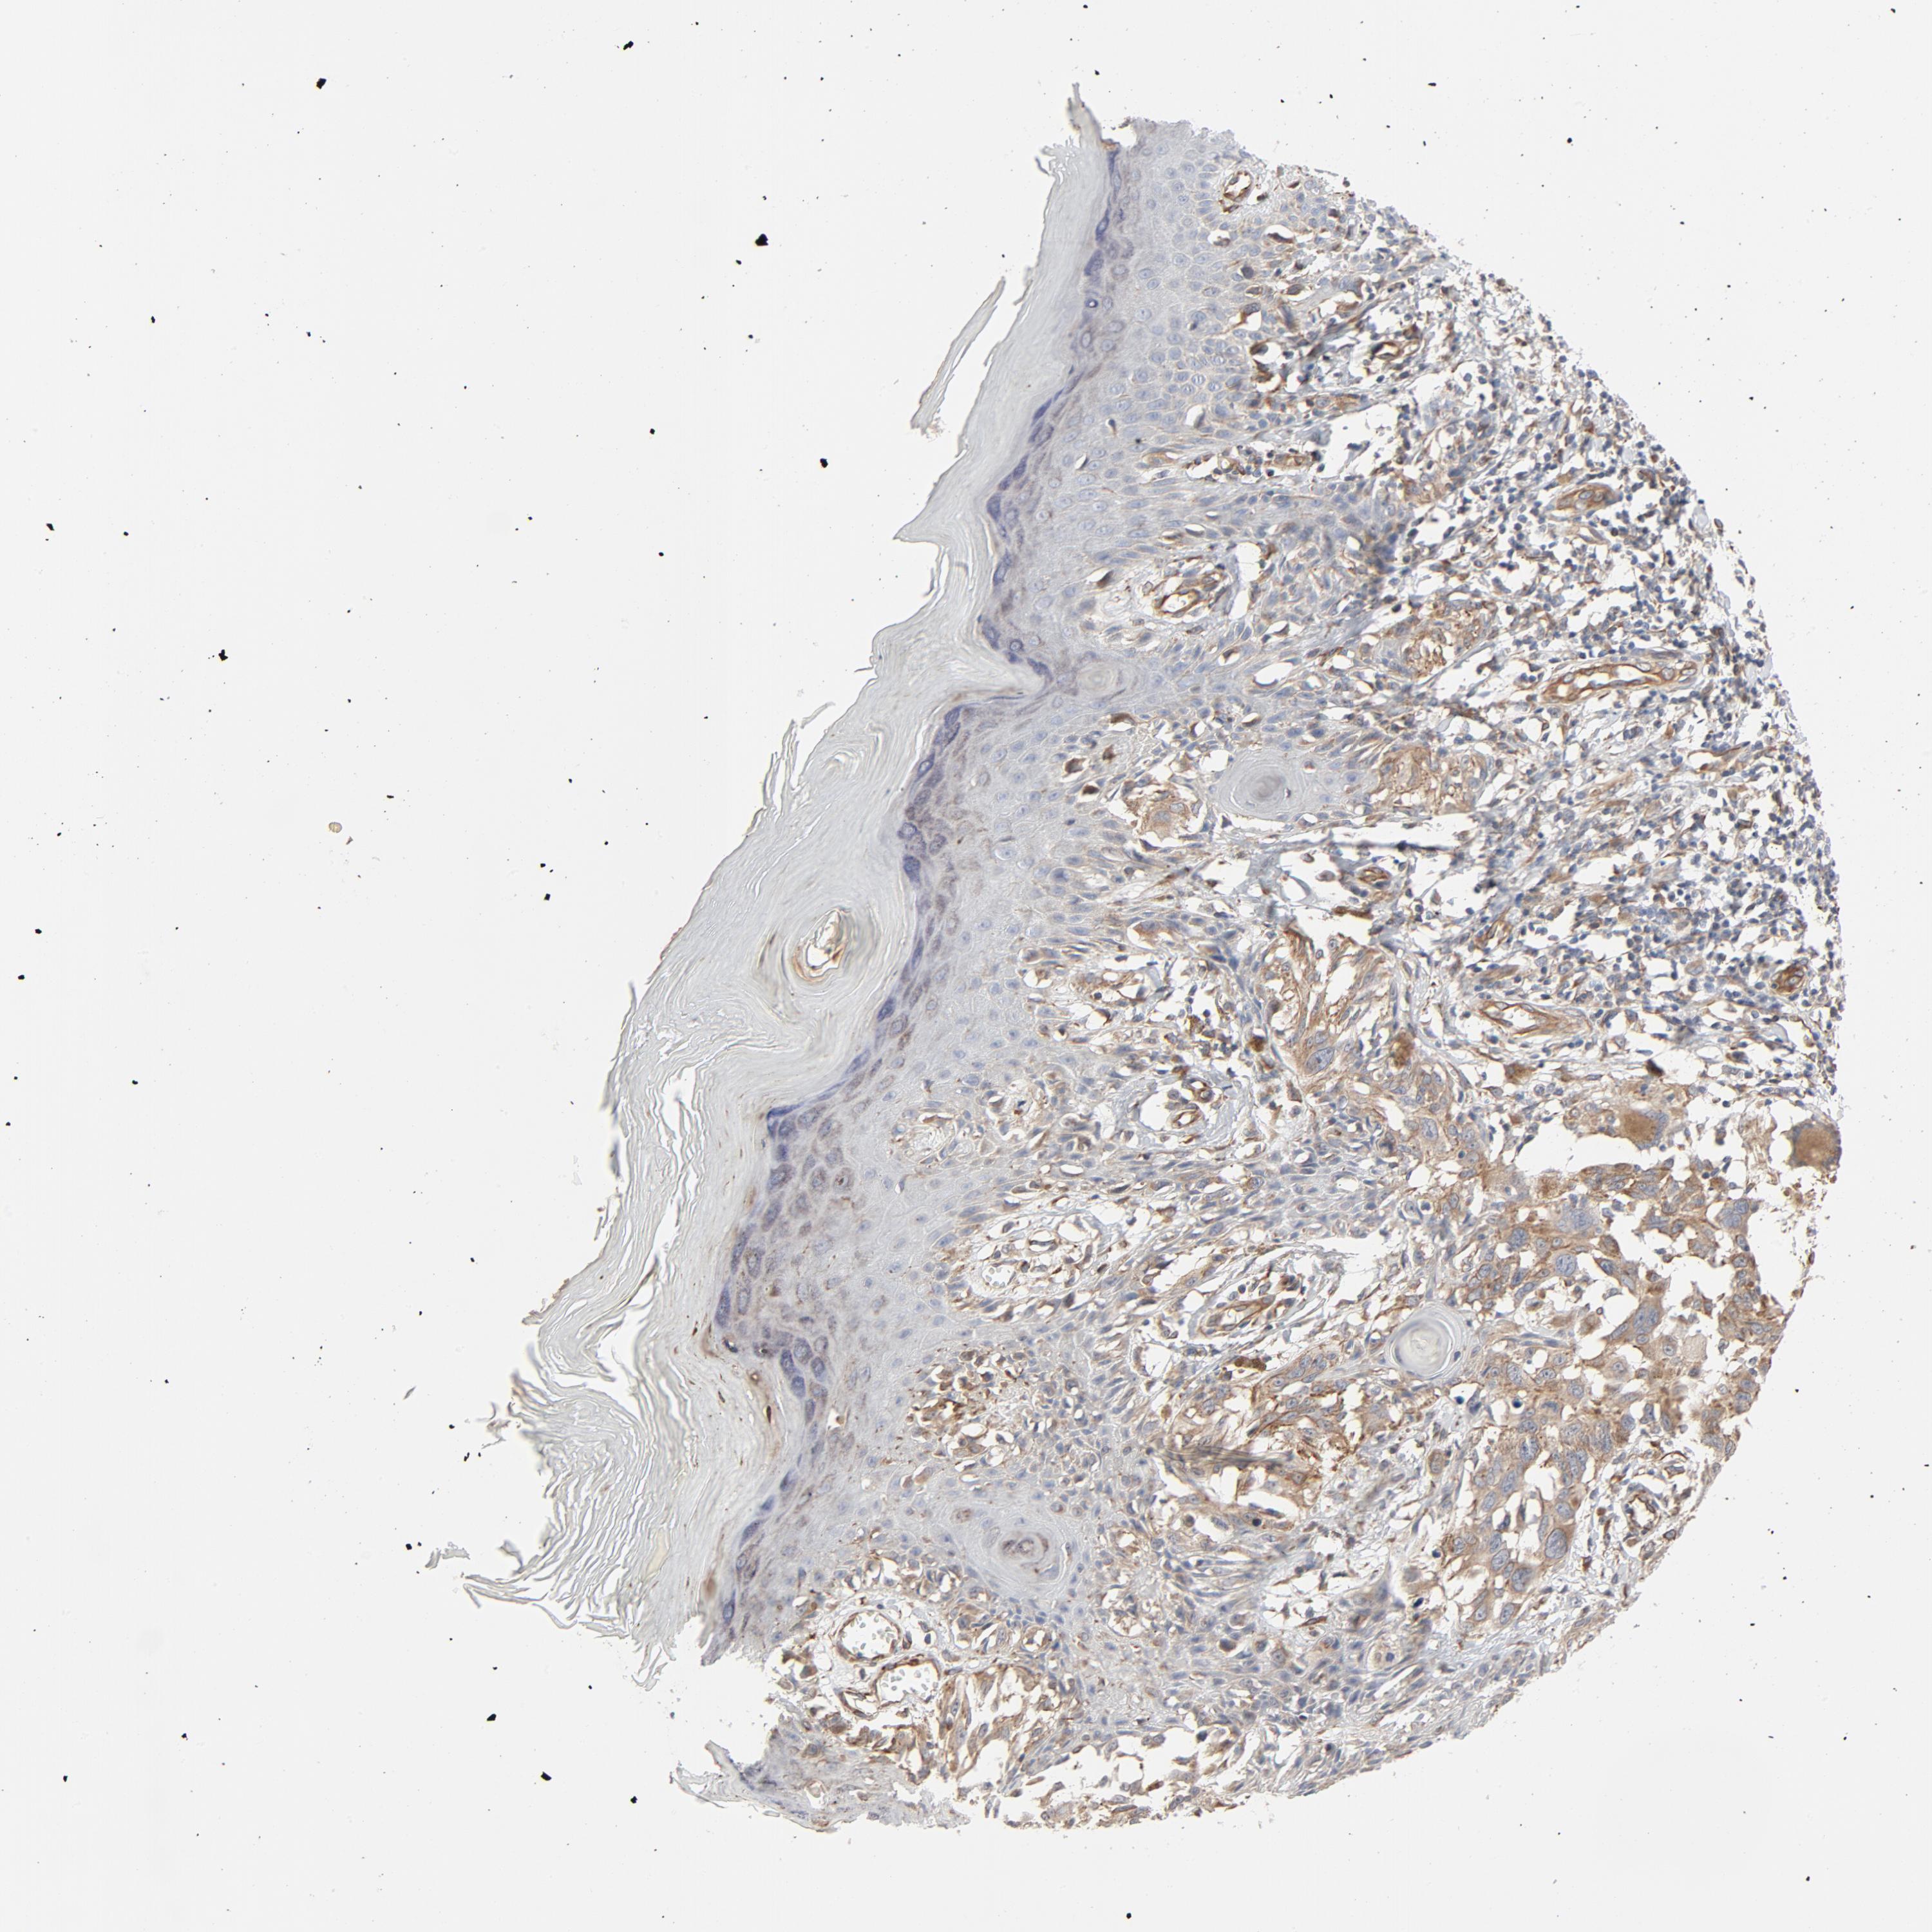

MELANOMA - Protein expressioni

A mouse-over function shows sample information and annotation data. Click on an image to view it in a full screen mode. Samples can be filtered based on level of antibody staining by selecting one or several of the following categories: high, medium, low and not detected. The assay and annotation is described here.

Note that samples used for immunohistochemistry by the Human Protein Atlas do not correspond to samples in the TCGA dataset.

Antibody stainingi

Antibody staining in the annotated cell types in the current human tissue is reported as not detected, low, medium, or high, based on conventional immunohistochemistry profiling in selected tissues. This score is based on the combination of the staining intensity and fraction of stained cells.

Each image is clickable and will lead to virtual microscopy that enables deeper exploration of all samples and also displays staining intensity scores, fraction scores and subcellular localization as well as patient and tissue information for each sample.

Antibody HPA003747

Antibody HPA019769

Staining

High

Medium

Low

Not detected

Intensity

Strong

Moderate

Weak

Negative

Quantity

>75%

75%-25%

<25%

None

Location

Nuclear

Cytoplasmic/membranous

Cytoplasmic/membranous,nuclear

Malignant melanoma, NOS

Malignant melanoma, Metastatic site